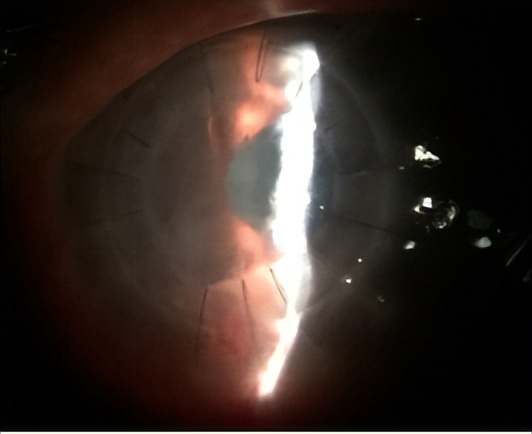

手术前,患者情况:

DALK治疗后1天,患者恢复情况:

DALK治疗后4周,患者情况:

DALK治疗后6个月,患者情况:

对于该患者的术后治疗,邓教授提出如下建议: